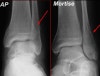

AP, lateral, Mortise view를 보면 대부분의 골절이 진단됩니다.

돌림손상 시에는 거골 바깥쪽 관절면의 골연골성 골절이 일어날 수 있습니다. Mortise view에서 가장 잘 나타나며 복합골절 평가 시에는 CT가 필요할 수 있습니다.

X-ray : 양과 골절(Bimalleolar fracture)